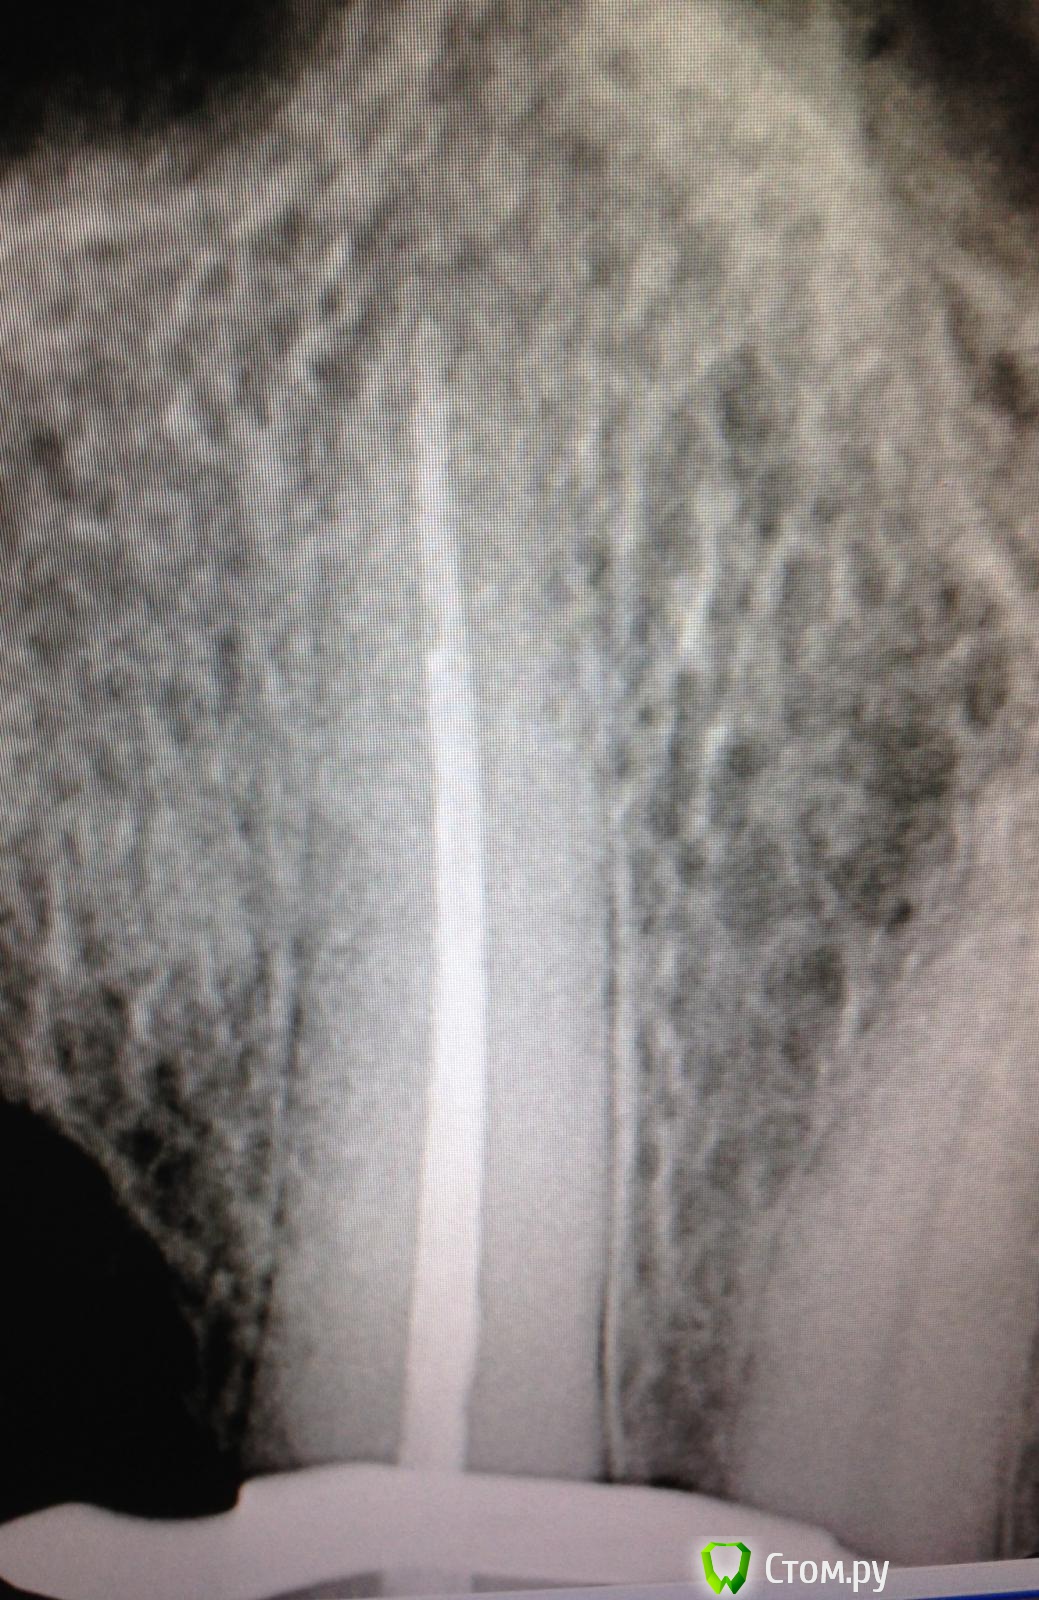

SSTi Опубликовано 7 октября, 2014 Автор Поделиться Опубликовано 7 октября, 2014 Как я не люблю широкие каналы! Понял это сегодня. 11. Сломан зуб давно. Болел. Потом не болет и тд. Стандартно. Весь в зарослях из десны. Сделали снимок. Ну, думаю, широкий и широкий. Ну и круто.Убрал десну. Феррул есть. Одел коффер. Преп. Вскрыли полость - там труп пульпы выглядывает и машет. Убрал эту красоту. Помылся. Померился. Машинными файлами посреб стенки, но толку мало. Начал делать уступ - 50 маленький. 55 мал. 60 мал, 70 мал. 80 - и тут я хоть уперся чуточку. Сделал упор как смог. Еще вымылся (мылись час в общей сложности). Латералка. Вот лучше бы семерку полечил, чем такую единицу. 1 Ссылка на комментарий

SSTi Опубликовано 7 октября, 2014 Автор Поделиться Опубликовано 7 октября, 2014 П.с. Был в шоке от гутты. 80 номер торчал из линейки калибровойной на 3.5 мм примерно. Как так то??? Ссылка на комментарий